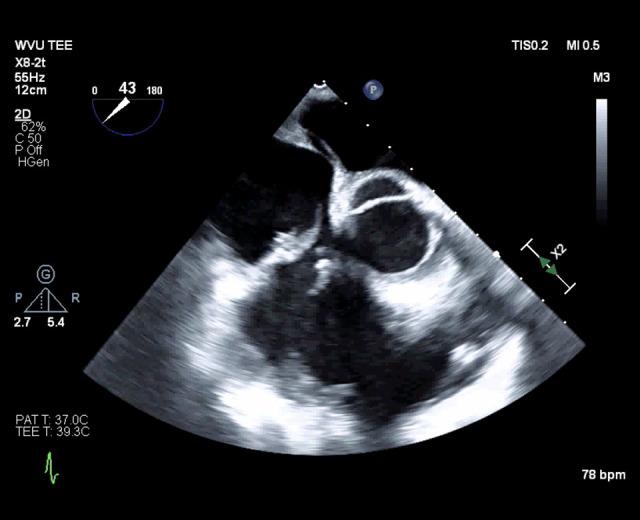

一位 34 岁男性静脉药物使用者,第三次三尖瓣心内膜炎发作,经重复瓣膜手术治疗。

A 34-Year-Old Male Intravenous Drug User with a Third Episode of Tricuspid Valve Endocarditis Treated with Repeat Valve Surgery.

病例报告

一名 34 岁男性,有静脉注射毒品史,因感染性心内膜炎在不到 7 个月的时间内进行了 3 次三尖瓣手术。他说他在第一次手术前没有注射过毒品,他有一个强大的社会支持系统,并且每次都完成了术后抗生素治疗方案。然而,在他最后一次手术前,患者的尿液药物筛查呈阿片类药物阳性,而没有记录的阿片类药物处方。3 次术中标本的病理报告显示每次都有不同的病原体。随后进行了广泛的跨专业讨论。